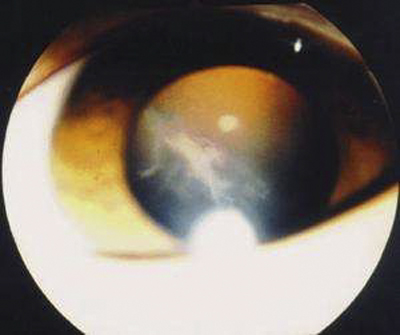

飛蚊症圖片

飛蚊症

飛蚊症

飛蚊症

飛蚊症

飛蚊症